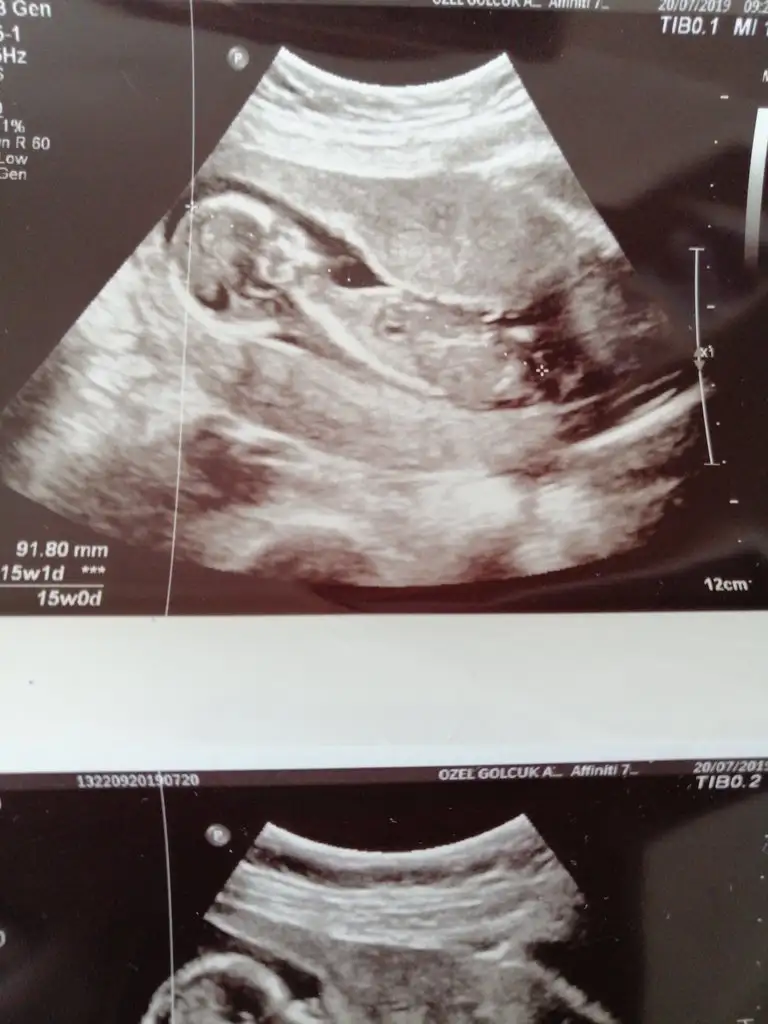

Bu usg saha öncede yorumladım sanki erkek gibiYorumlarinizi alabilir miyim? 12+4 teki usg miz

Kız canım zaten nub olmaz 13+4 haftada ya pıtış ya pipi olur bu bebek bence kız dr tahmin etmediniMerhaba bugün devlet hastanesinde kontolüm vardı cinsiyet için erken dedi burda 13+4 yeniden cinsiyet tahmin edebilir misiniz ?

15 haftadasınız dr yorum yapmadımı 11 yada 12 hafta olmalı nub içinCocoChanelmademoiselle Ikra meyra M mely15 sizlerin yorumunu merak ediyorum bugün ki ultrason görüntüleri